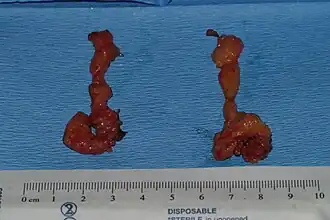

Extracted buccal fat | |

Removal of the buccal fat pad is also sometimes used to reduce cheek prominence, although this procedure may carry with it a significant risk of damage to the buccal branch of the facial nerve and the parotid ducts.[12]